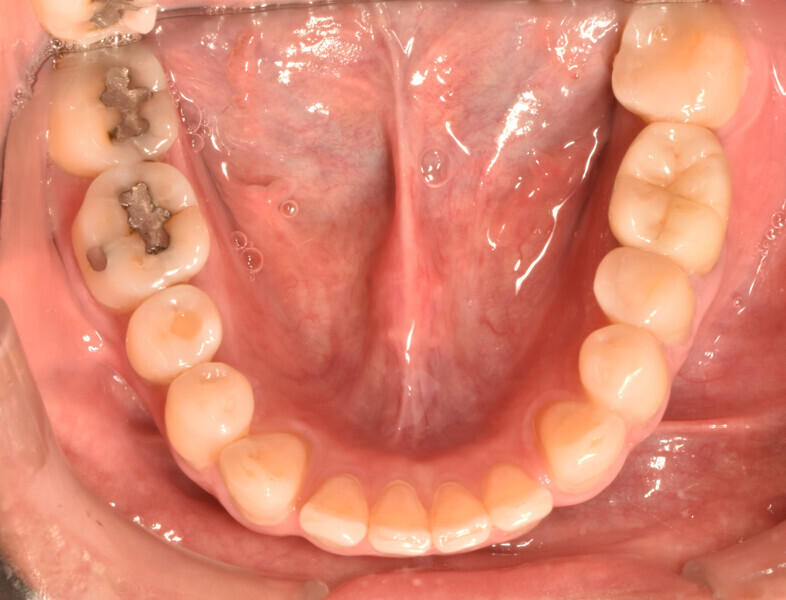

A 50-year-old patient with non-contributory systemic disease presented with the main complaint of pain on mastication. He reported having had a direct restoration on the mandibular left first molar six months earlier. On clinical and radiographic examination, a large, overextended amalgam Class II filling was observed as well as a J-shaped radiolucency on the distal aspect of the tooth (Fig. 1). A buccal swelling oriented distally was also present, as were characteristics of occlusal wear compatible with bruxism on the patient’s dentition. The tooth had pain on percussion and responded negatively to electrical and thermal stimulus tests. When probing in the region of the abscess, a 9 mm isolated pocket was identified (Fig. 2). The tooth was diagnosed with pulpal necrosis and periapical abscess and a suspected VRF. To confirm the presumptive diagnosis, an access cavity was prepared under dental dam isolation and under the dental operating microscope. When the previous restoration was removed, a longitudinal fissure line was detected on the distal aspect of the pulpal floor at higher magnification (10×).

Fig. 1a

Fig. 1b

Fig. 2